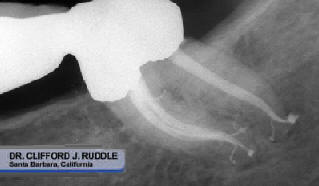

Sistemas de conductos limpios y permeables,  proporcionan el éxito de la obturación 3D  a largo plazo (Figuras 11- 14).

Figura 14